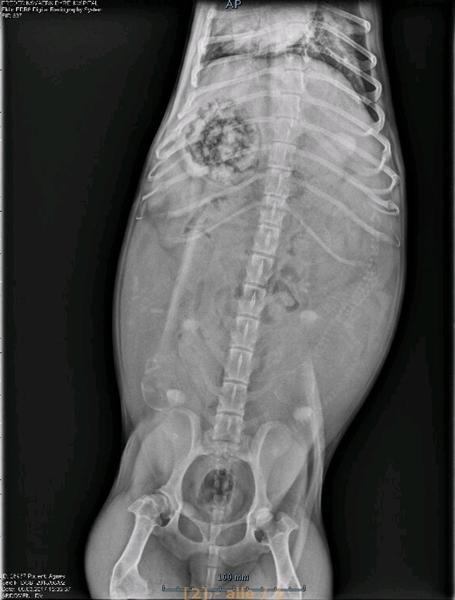

Hvor ser man hvalpene på sådan et scanningsbillede?

Hvor "ligger" hvalpene så på billedet?

så kan jeg måske bedre vide hvad jeg skal kigge efter næste gang.

Alt mellem 3-8

Men 10-11 ses ind imellem

Agnes er standard, men miniature og dværg får sjældent mere en 5 stykker oftest færre.